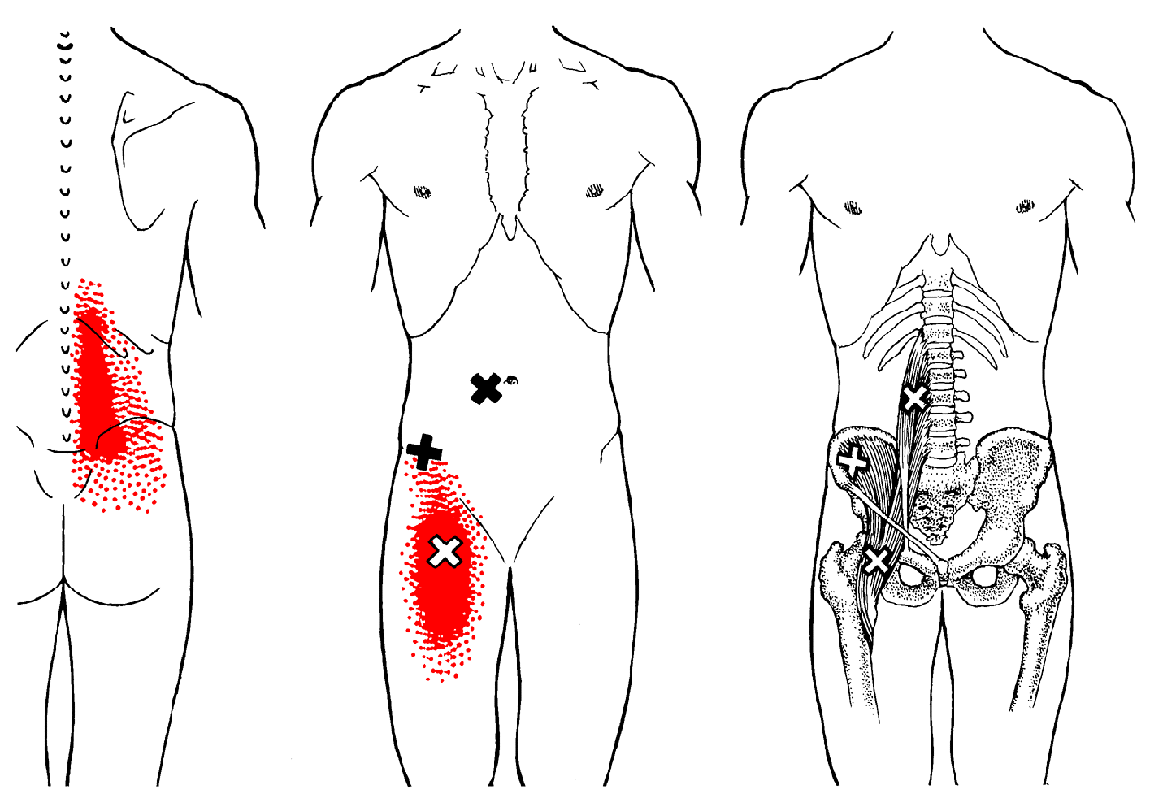

Iliopsoas Trigger Point Diagram Primary Symptoms :

Anterior Thigh Pain

Appendicitis-like Pains

Groin Pain

Iliosacral Pain

Lumbar Pain

Secondary Symptoms :

Thoracic Back Pain4. 참고문헌